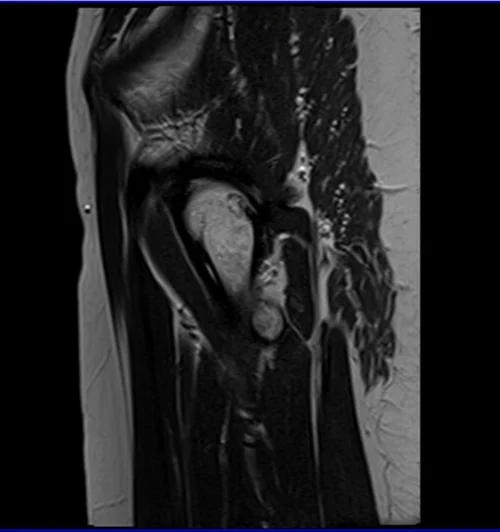

mri hips sag t2 image 4 - MRI